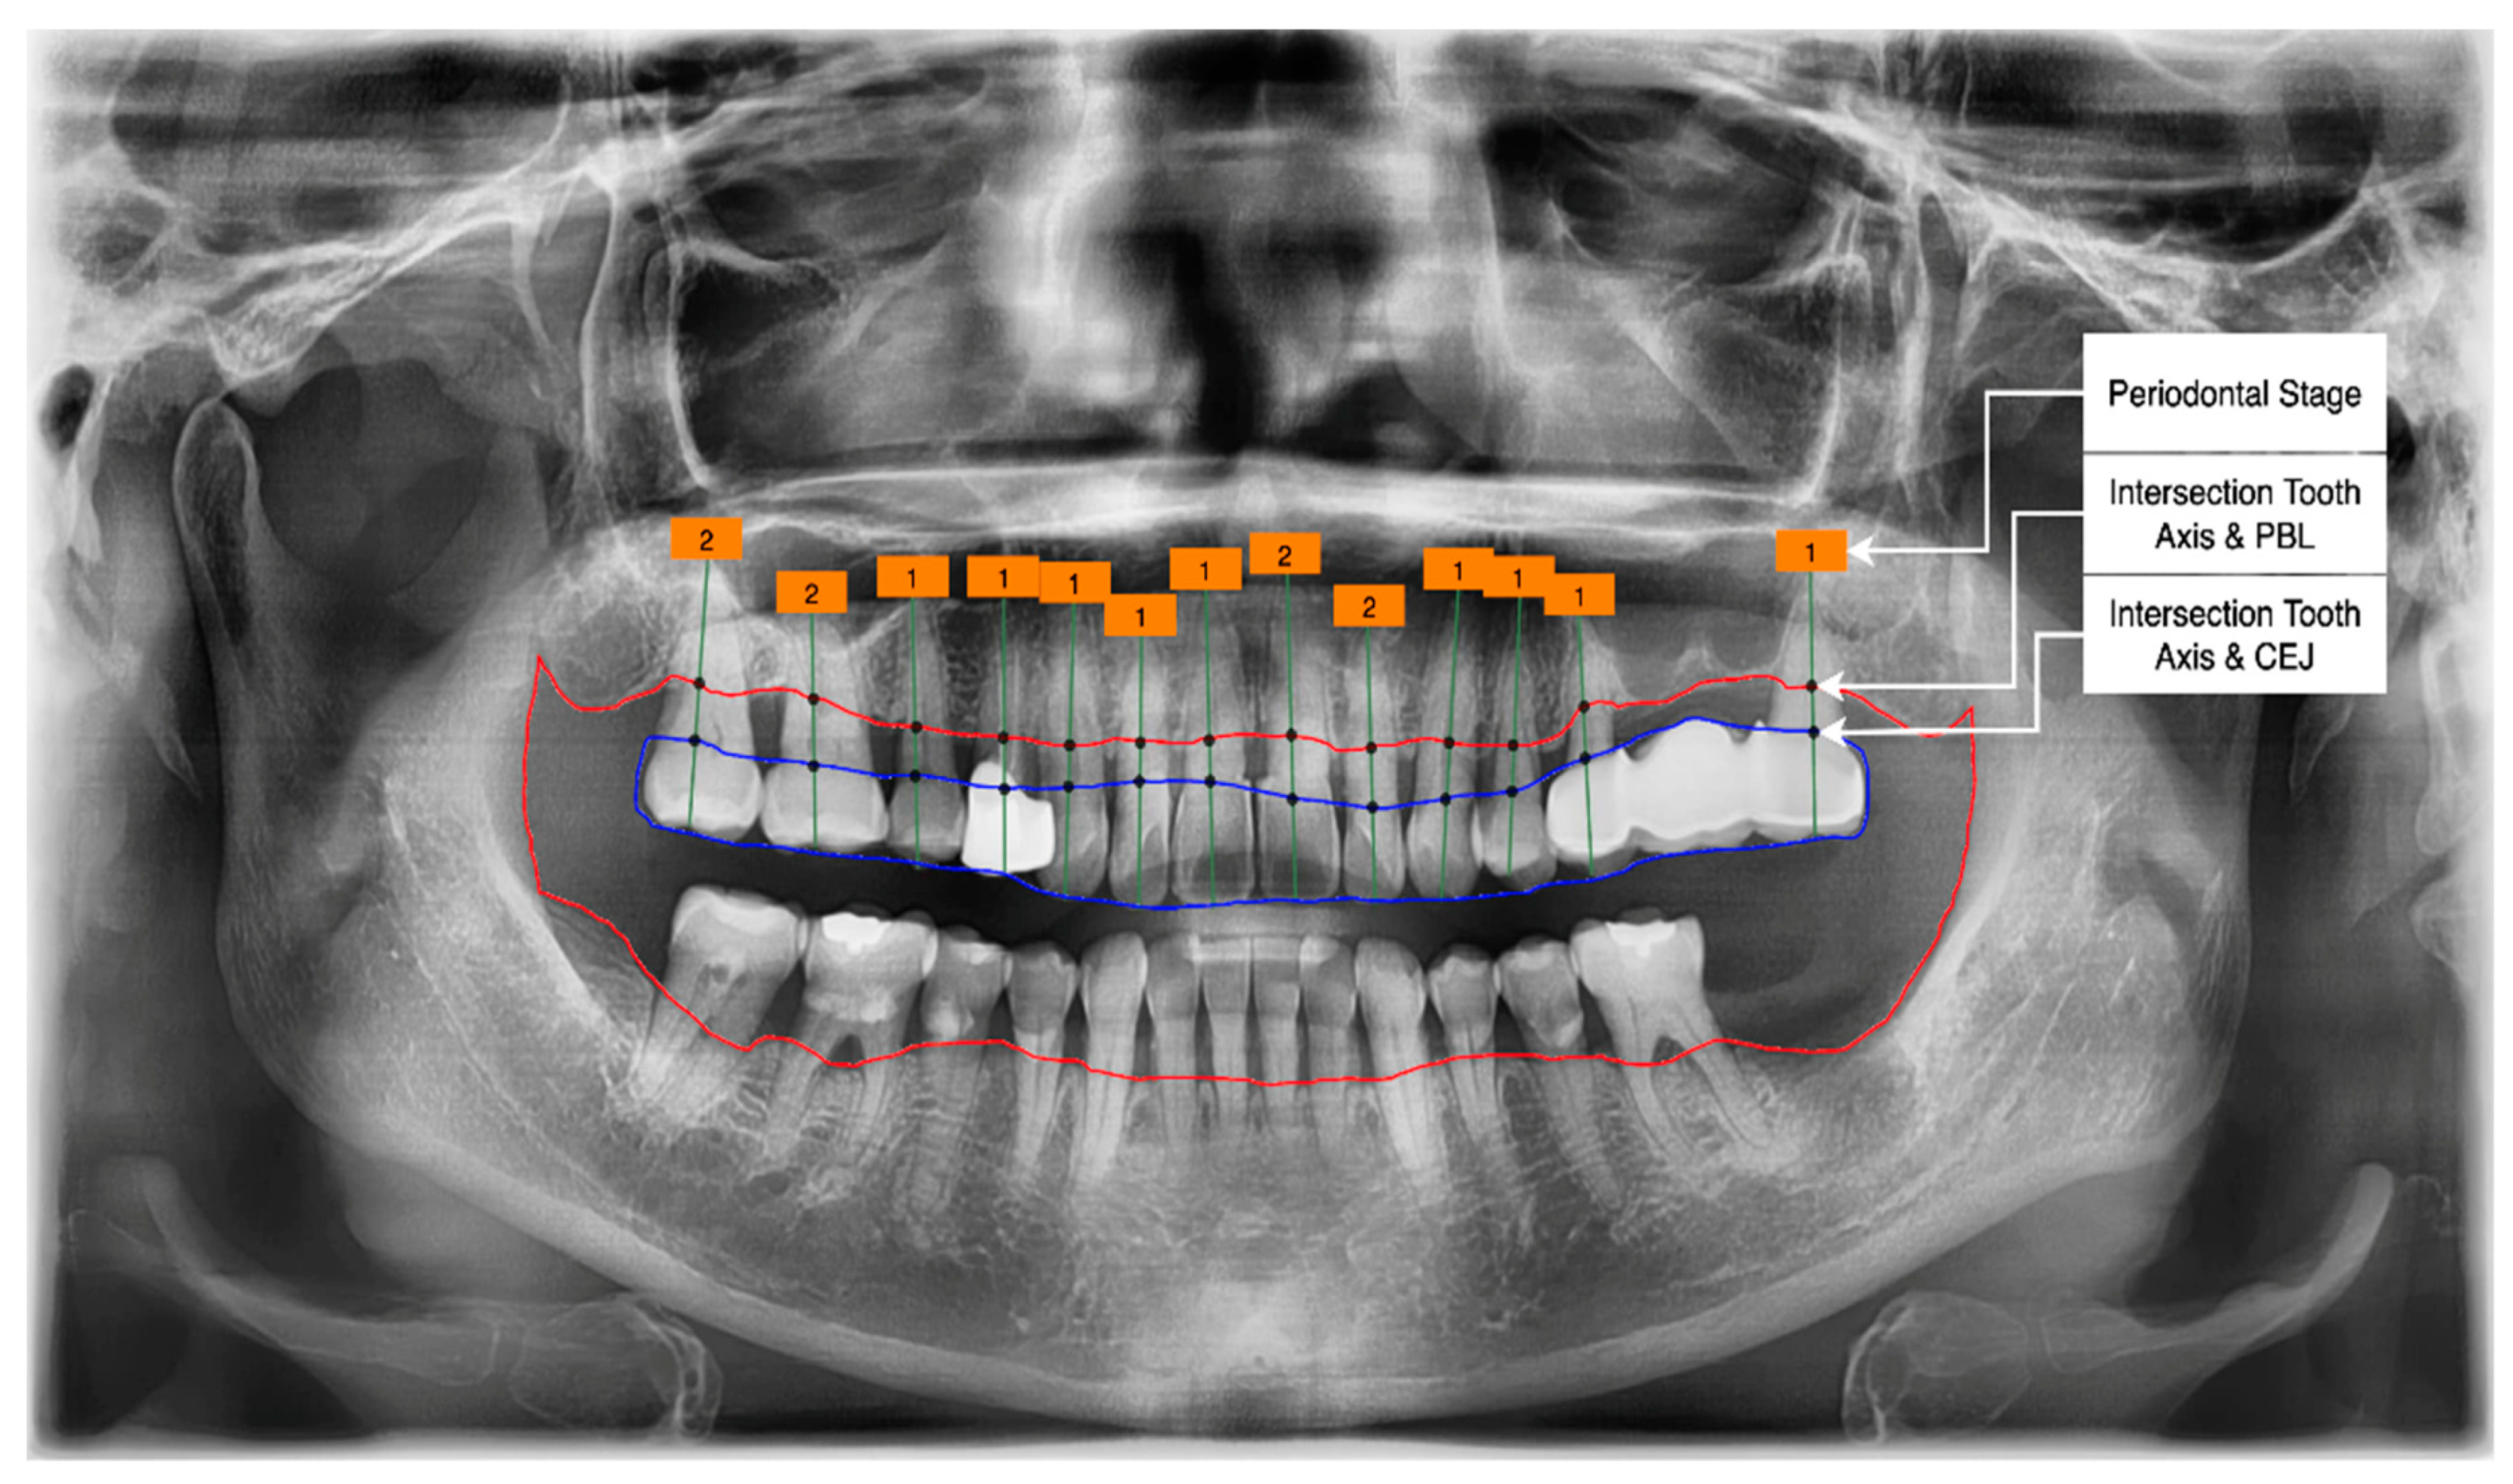

- Get the intersection of the PBL’s upper side and the tooth’s middle axis.

- Get the intersection of the CEJ’s upper side and the tooth’s middle axis.

- Calculate the length from those two intersections (known as the RBL length).

- Calculate the RBL percentage from the RBL length and tooth root.

3.2. PBL and CEJ Boundary Detection through U-Net

Classification of the PBL by Percentage Rate Analysis